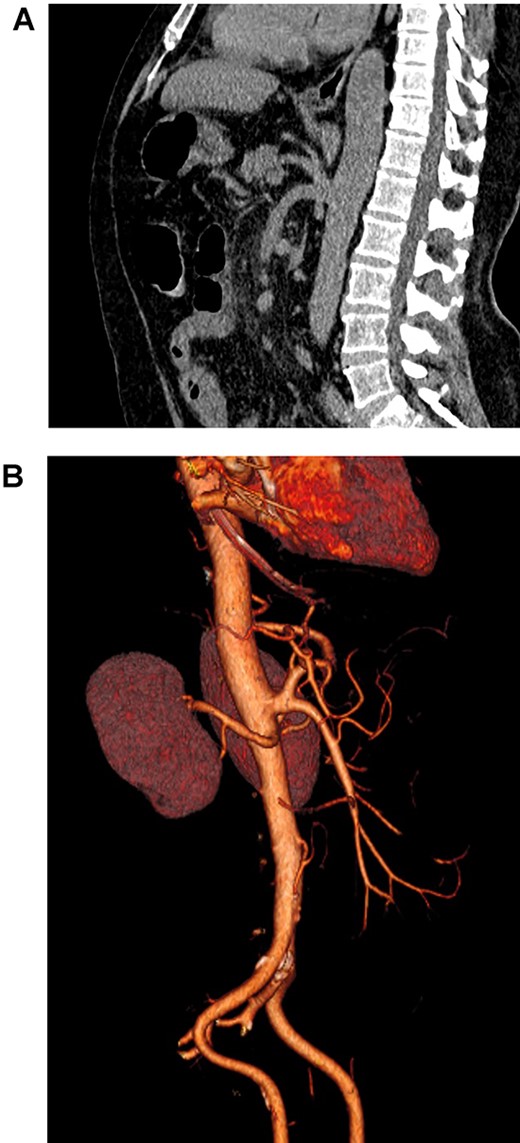

An angio-3D reconstruction of a patient’s CT scan was performed to rule out any vascular disease; although no thrombus or embolus was discovered, a vascular malformation of the superior mesenteric artery was found. The superior mesenteric artery and the celiac trunk arise from a common trunk, the celiacomesenteric trunk (Fig. 3A and B).

(A). Abdominal CT, showing the celiacomesenteric trunk. (B). Abdominal 3D reconstruction, revealing the vascular variation.